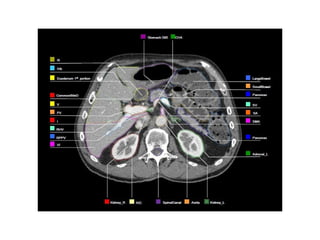

OAR Contouring for HCC

• At minimum, these structures are required to be contoured at the

level of the PTV and over any region received > 10 Gy.

• An upper abdominal/liver atlas, posted at the ITC website, may be

used as a guide for contouring.

• all portions of the duodenum are recommended to be contoured